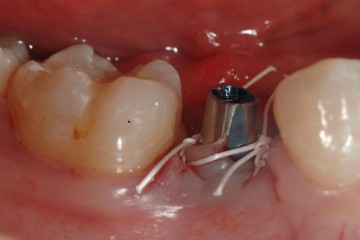

患者許小姐,左下第二小臼齒,因為深度蛀牙,因而牙齒被拔除(圖一、圖二、圖三),患者由於是一位高二學生,深怕缺牙久了若不處理,鄰牙可能倒過來(圖四),但若以傳統假牙修復,還需再磨完整的自然牙(圖五),經轉診至本診所尋求人工植牙。

圖三 |

圖六為使用德國Revois植體系統,由於植入的角度相當理想,直接將植牙的支柱放入,一週拆線後放入臨時假牙,讓人工植牙持續穩定的受力,不斷的進行骨整合。